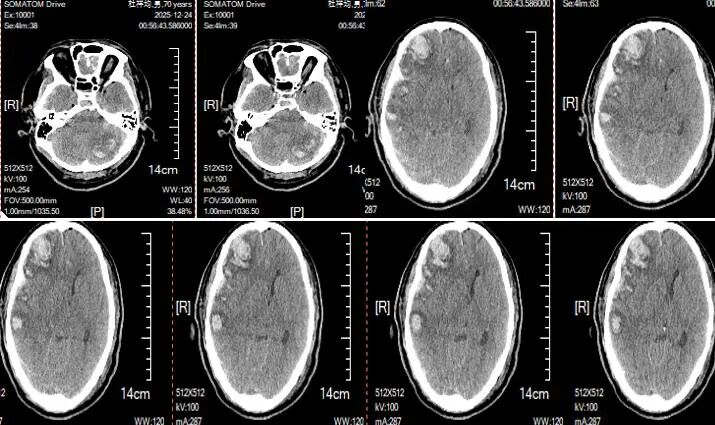

入院时颅脑CT平扫 :多发脑挫伤